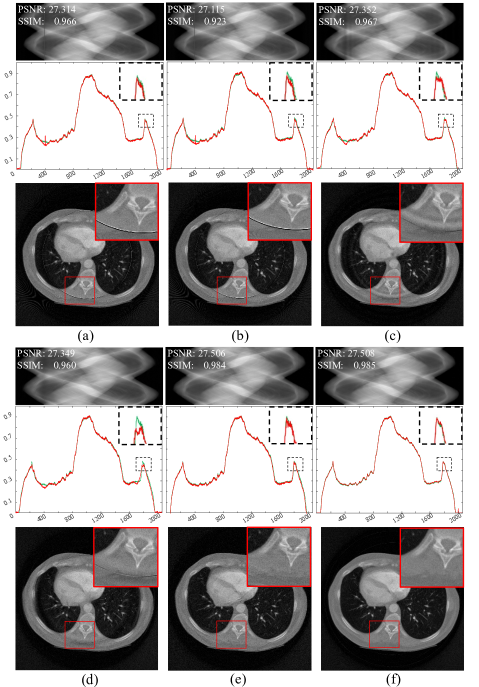

Figure 10: Comparison experiments with real data. (a) Combination method. (b) Method from [34]. (c) Method from [21]. (d) Normalization method. (e) FFT method. (f) W-FFT method. (g) Regularization method. (h) Proposed method. The display range is [0, 3.144] for the sinograms and [0, 0.010] for the CT images. The zoom-in view on the left shows [0, 0.010], and on the right, it shows [0.0016, 0.003].

Figures 10 (a), (b), (c), and (h) show the results of stripe artifact removal from the sinogram containing black gaps in Fig. 9 (a). All methods successfully removed the black stripes and reduced other stripe artifacts. The results of the combination method [14] in Fig. 10 (a) demonstrate its effectiveness in removing stripe artifacts. The overall image is clear, and details are well-preserved. However, in the local zoomed-in regions, some ring artifacts remain. Fig. 10 (b) shows the result after applying flat-field correction and linear interpolation for defective pixels (black gaps), followed by TV-L1subscript𝐿1L_{1} aG filtering. The results indicate that while details are well preserved, noticeable ring artifacts remain in the local zoomed-in regions. Fig. 10 (c) uses a dual-domain regularization iterative method. The reconstructed results still show slight ring artifacts in the local zoomed-in regions. Fig. 10 (h) presents the results of the proposed method, where defective pixels (those at the black gaps) were not involved in the neural network training. These defective pixel values were predicted by the network 𝐅𝚯subscript𝐅𝚯\mathbf{F}_{\mathbf{\Theta}}. The proposed method can maintain image continuity while filling gaps and effectively controlling ring artifacts. Figures 10 (d) to (g) show the experiments on stripe artifact removal from the sinogram after linear interpolation of the black gaps in Fig. 9 (b). Although these methods improved the quality of the reconstructed images and reduced ring artifacts to some extent, residual ring artifacts can still be observed in the local zoomed-in regions. The proposed method in Fig. 10 (f) best preserves image continuity and reduces ring artifacts.

In summary, when comparing the methods in Fig. 10, the method in Fig. 10 (a) is relatively complex, achieving good stripe artifact removal results but still leaving slight ring artifacts. The methods in Fig. 10 (b) and Fig. 10 (c) require extensive parameter tuning to achieve satisfactory results. Methods in Fig. 10 (d) to Fig. 10 (g) leave some residual ring artifacts. Fig. 10 (h) provides the best ring artifact removal and the clearest reconstructed image. Comparative analysis shows that the proposed method effectively removes ring artifacts, whereas other methods leave varying degrees of ring traces in the reconstructed images.